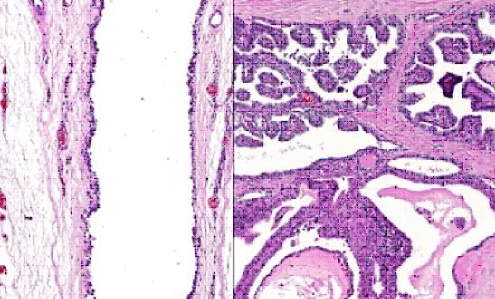

The patient underwent neck exploration for removal of the mass. At the time of operation two cystic masses were found at the right mid jugular region (3.0 x 2.7 cm in diameter) and right supraclavicular region (8.6 x 5.0 cm in diameter) with no adjacent organ invasion and no association to hyoid bone. The patient developed chyle leakage on the first post- operative day, but resolved after five days of conservative treatment. Histopathological examination showed cystic spaces lined with simple columnar epithelium cells and foci of thyroid tissue at the outer aspect of the cyst wall. A small papillary carcinoma was present in this area which showed finger-like branching papillary projections (arrows) lined by neoplastic cells (Figure 3).

Click below to enlarge

Figure 3: Simple columnar epithelial cells of thyroglossal duct cyst. A) Foci of thyroid tissue which presented at outer aspect of cyst wall and, B) transforms to papillary carcinoma (arrow)..